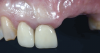

A systemically healthy 40-year-old male patient presented with a maxillary anterior vertical defect (Figure 1 and Figure 2). The patient stated that a previous bone grafting procedure was attempted in this area, but failed. The treatment plan involved a staged guided bone regeneration, the placement of three dental implants 9 months after bone augmentation, and soft-tissue grafting prior to implant loading to augment peri-implant soft-tissue thickness and keratinized mucosa width.

Fig 1. Frontal clinical view at baseline.

Figure 1